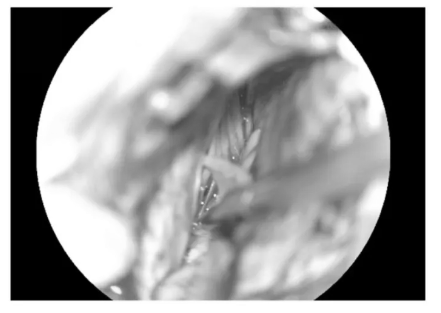

▼充分游离后组颅神经与绒球

▼逐步暴露椎动脉、PICA及延髓侧方

▼分离延髓表面血管

▼从后组颅神经与PICA之间进入延髓侧方

▼可见黄染的含铁血黄素沉积带

▼可见粗大的引流静脉,予以保护

▼沿周边黄染的含铁血黄素沉积带分离肿瘤

▼肿瘤标本完整取出

▼瘤腔止血

▼袖珍的延髓表面造痿口

▼水密缝合硬脑膜